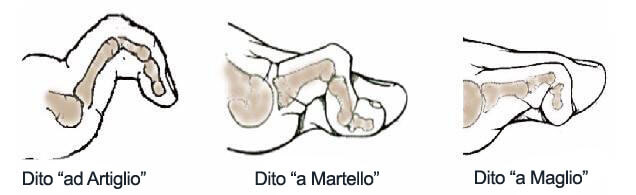

Deformità delle Ultime Dita

Possono derivare da numerose condizioni, comprendenti: malformazioni congenite, disordini neuromuscolari, artriti infiammatorie e traumi che si accomunano per la presenza di dolore acuto e irritazione del dito dovuta all’attrito contro la scarpa o contro un dito vicino. Di conseguenza si possono generare le seguenti deformità: